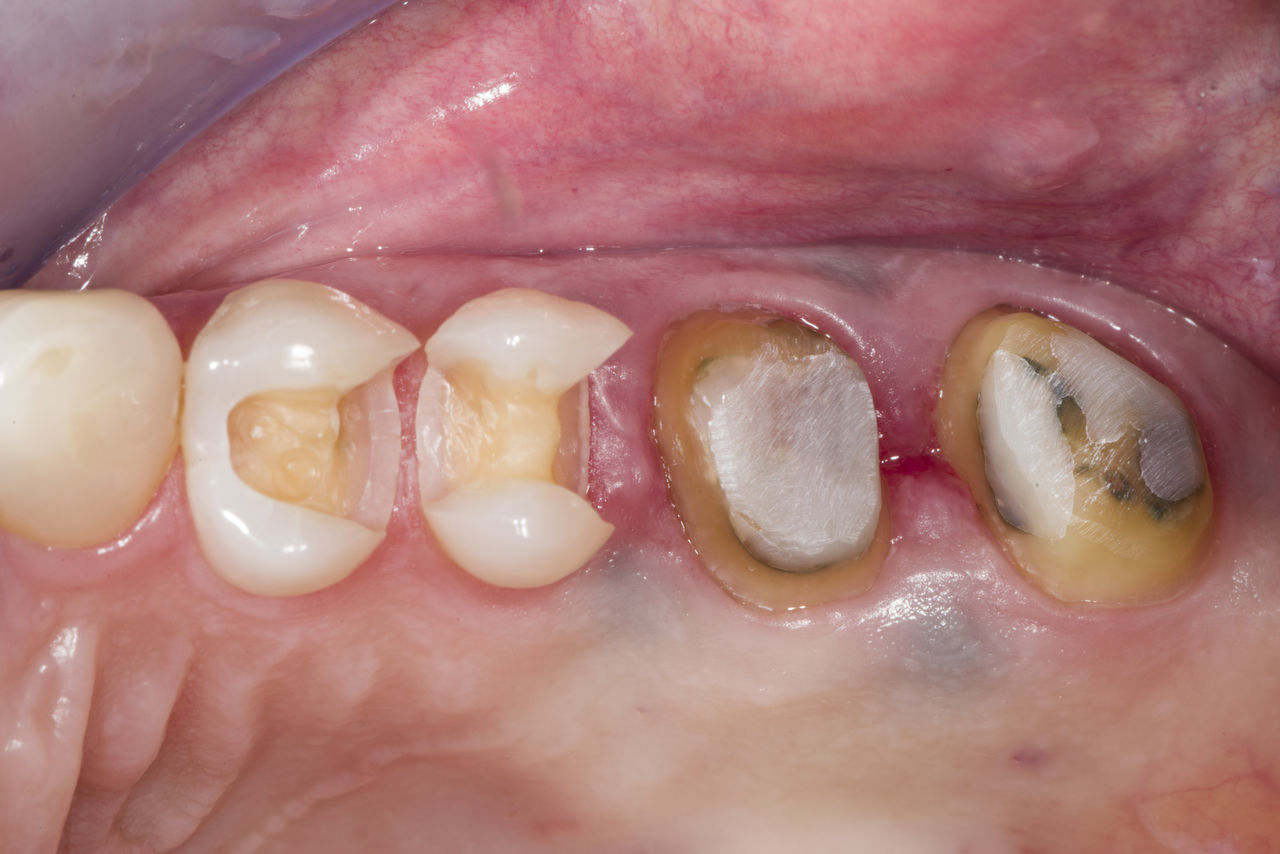

Amélogenèse imparfaite

Restauration complète de la bouche avec 28 restaurations tout céramique

Un cas particulier et prolongé de malocclusion squelettique de classe II et d’amélogenèse imparfaite généralisée chez un adolescent a été référé pour une réhabilitation prothétique. L’objectif du traitement était de préparer la structure dentaire restante, d’éliminer les contre-dépouilles et de faire de la place pour des couronnes entièrement en céramique couvrant toute la dentine et simulant l’émail perdu.

Avant : Situation initiale avant le traitement orthodontie.

Après : Résultat final, 1 semaine après l’opération.